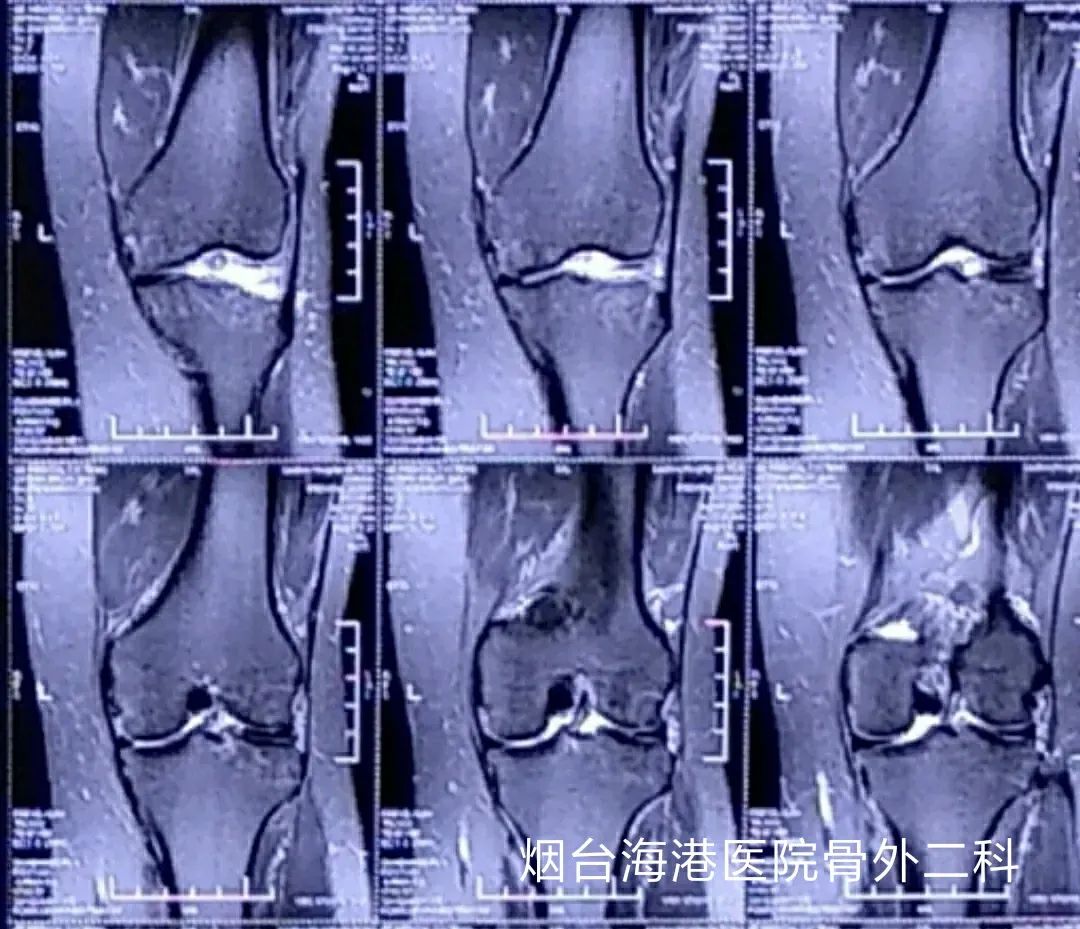

但是,经核磁共振检查后,结果却不典型,冠状位只有一个面能够看出半月板损伤,其余的图像均提示损伤很轻。而膝关节核磁共振检查只能够达到90%-95%的准确率,只有关节镜检查是诊断膝关节疾病的金标准,并且关节镜还具有治疗作用,手术中发现问题,可以一并进行处理。

手术很快开始了。在术中,柳医生在患者的膝关节两侧各做一长约0.6公分的切口;通过电脑屏幕,清晰的显示出了关节内的结构,通过仔细的检查,发现膝关节的外侧半月板自体部撕裂,撕裂的部分处于半月板的“白区”,漂浮于关节腔内;至此,杨女士膝关节绞索的始作俑者终于找到了,与医生术前判断的情况是一致的。